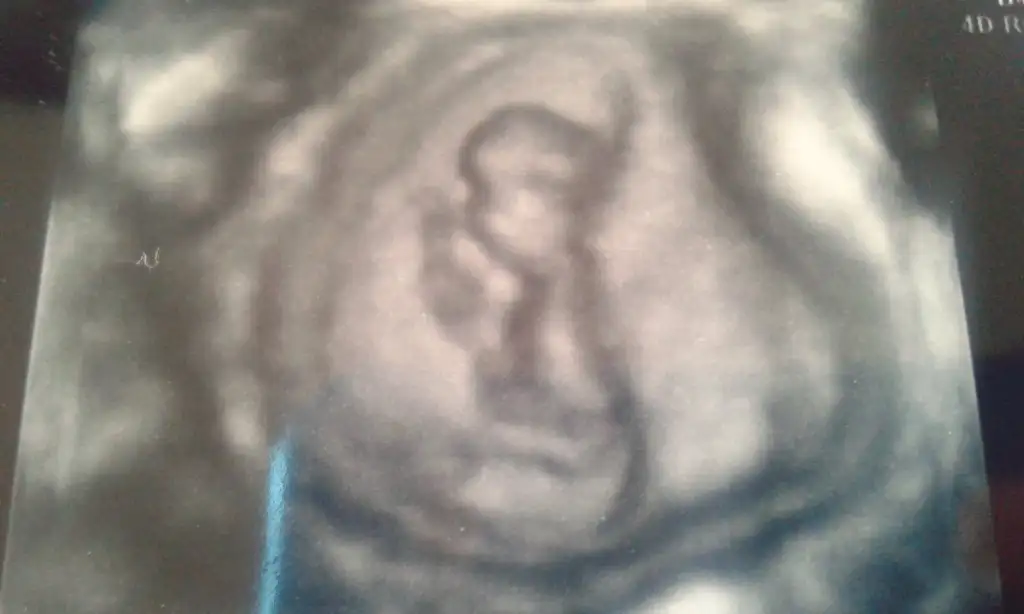

mrb arkadaşlar bugün 15 haftalık olduk kontrol vardı ve cinsiyetimize %51 den yüksek erkek dedi. resimler kalitesiz diyende var siz anlayabilirmisiniz merak beni öldürecek :)